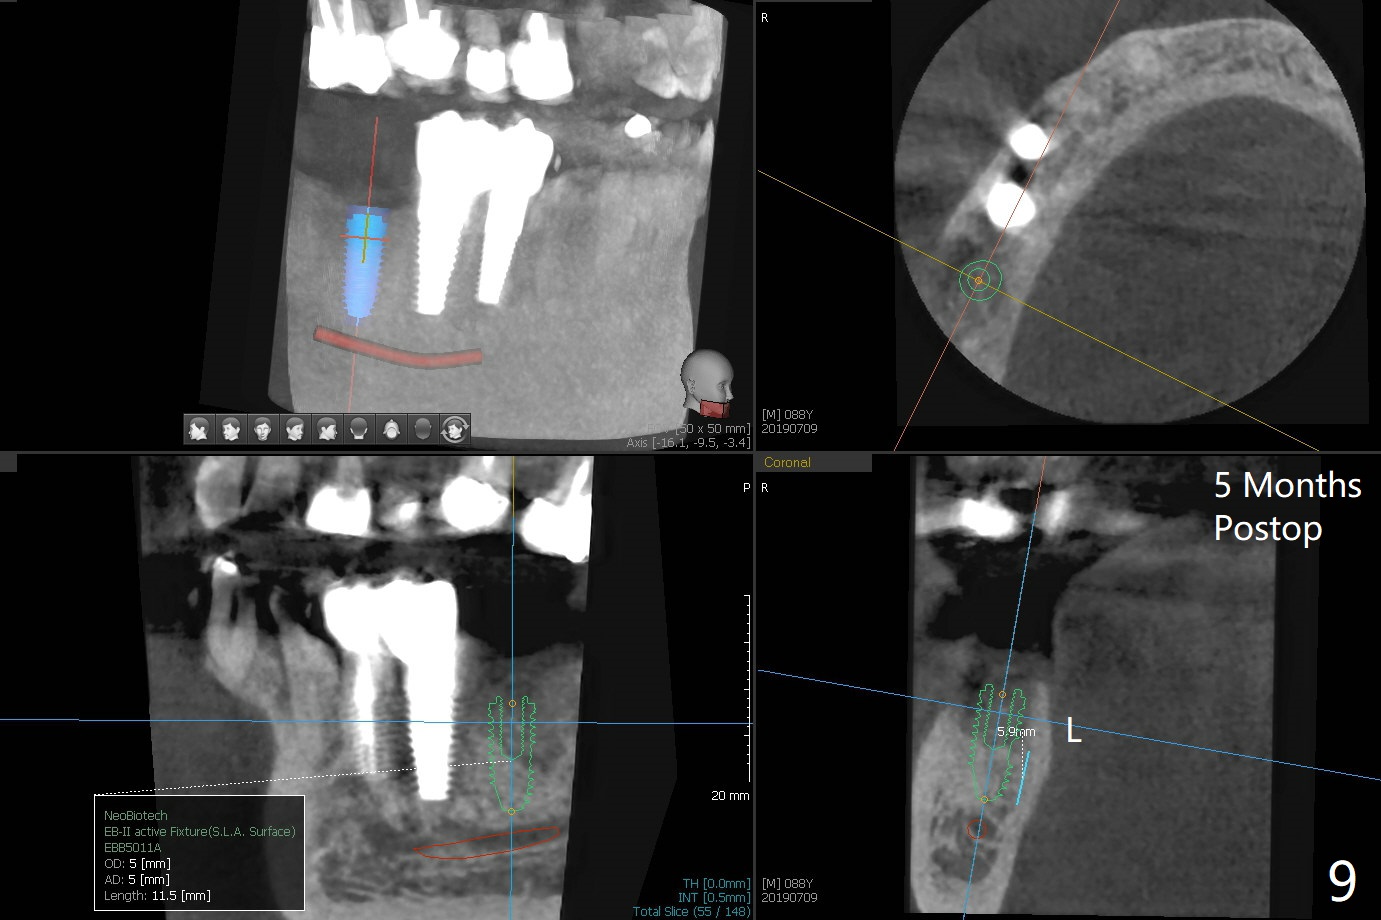

A 88-year-old man returns with pain and swelling (Fig.1), one year after diagnosis of #31 mesial root fracture. After discussion, the tooth is extracted with socket preservation (Vanilla graft mixed with Osteogen, covered with Osteogen plug and Collagen plug, Fig.2,3). The buccal crest is much lower than the lingual one. The socket opening reduces with resolution of 4-0 Chromic gut suture 1 week postop (Fig.4). The wound is wider with foul odor 2 weeks postop (data not shown). The socket and ridge shrink with loss of the bone graft 3 weeks postop (Fig.5). The bone volume reduces with buccal plate collapse 3 months postop (Fig.6,7). Immediate implant and provisional should be able to help restore the lost buccal plate. The buccal plate remains concave 5 months postop (Fig.8,9). The coronal section shows that there is space (Fig.10 *) buccal to the graft (G). A 2.0 mm pilot drill is used to create an initial osteotomy through the graft zone and in the beginning of the native bone (Fig.11,12). Use bone expanders (Fig.13 E) to push (arrowheads) and condense the graft bone and close the buccal gap. The apical portion of the osteotomy requires regular drills (Fig.14 D).